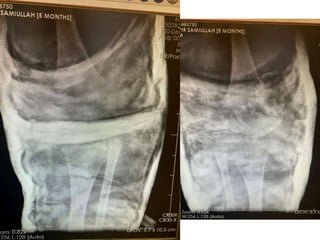

Phase-3: 2 marks

If the candidate orders some

investigations such as X-Ray show

him the X-Ray (and not the report)

and ask him:

1. What do you find on X-

Ray?

2. How will you proceed

further?

If the candidate reads X-Ray

correctly, draw referral lines and

request additional imaging show him

and ask why

CT / MRI

Phase-3: 2 marks Ifthe candidate orders some investigations such as X-Ray show him the X-Ray (and not the report) and ask him: 1. What do you find on X- Ray? 2. How will you proceed further? If the candidate reads X-Ray correctly, draw referral lines and request additional imaging show him and ask why CT / MRI